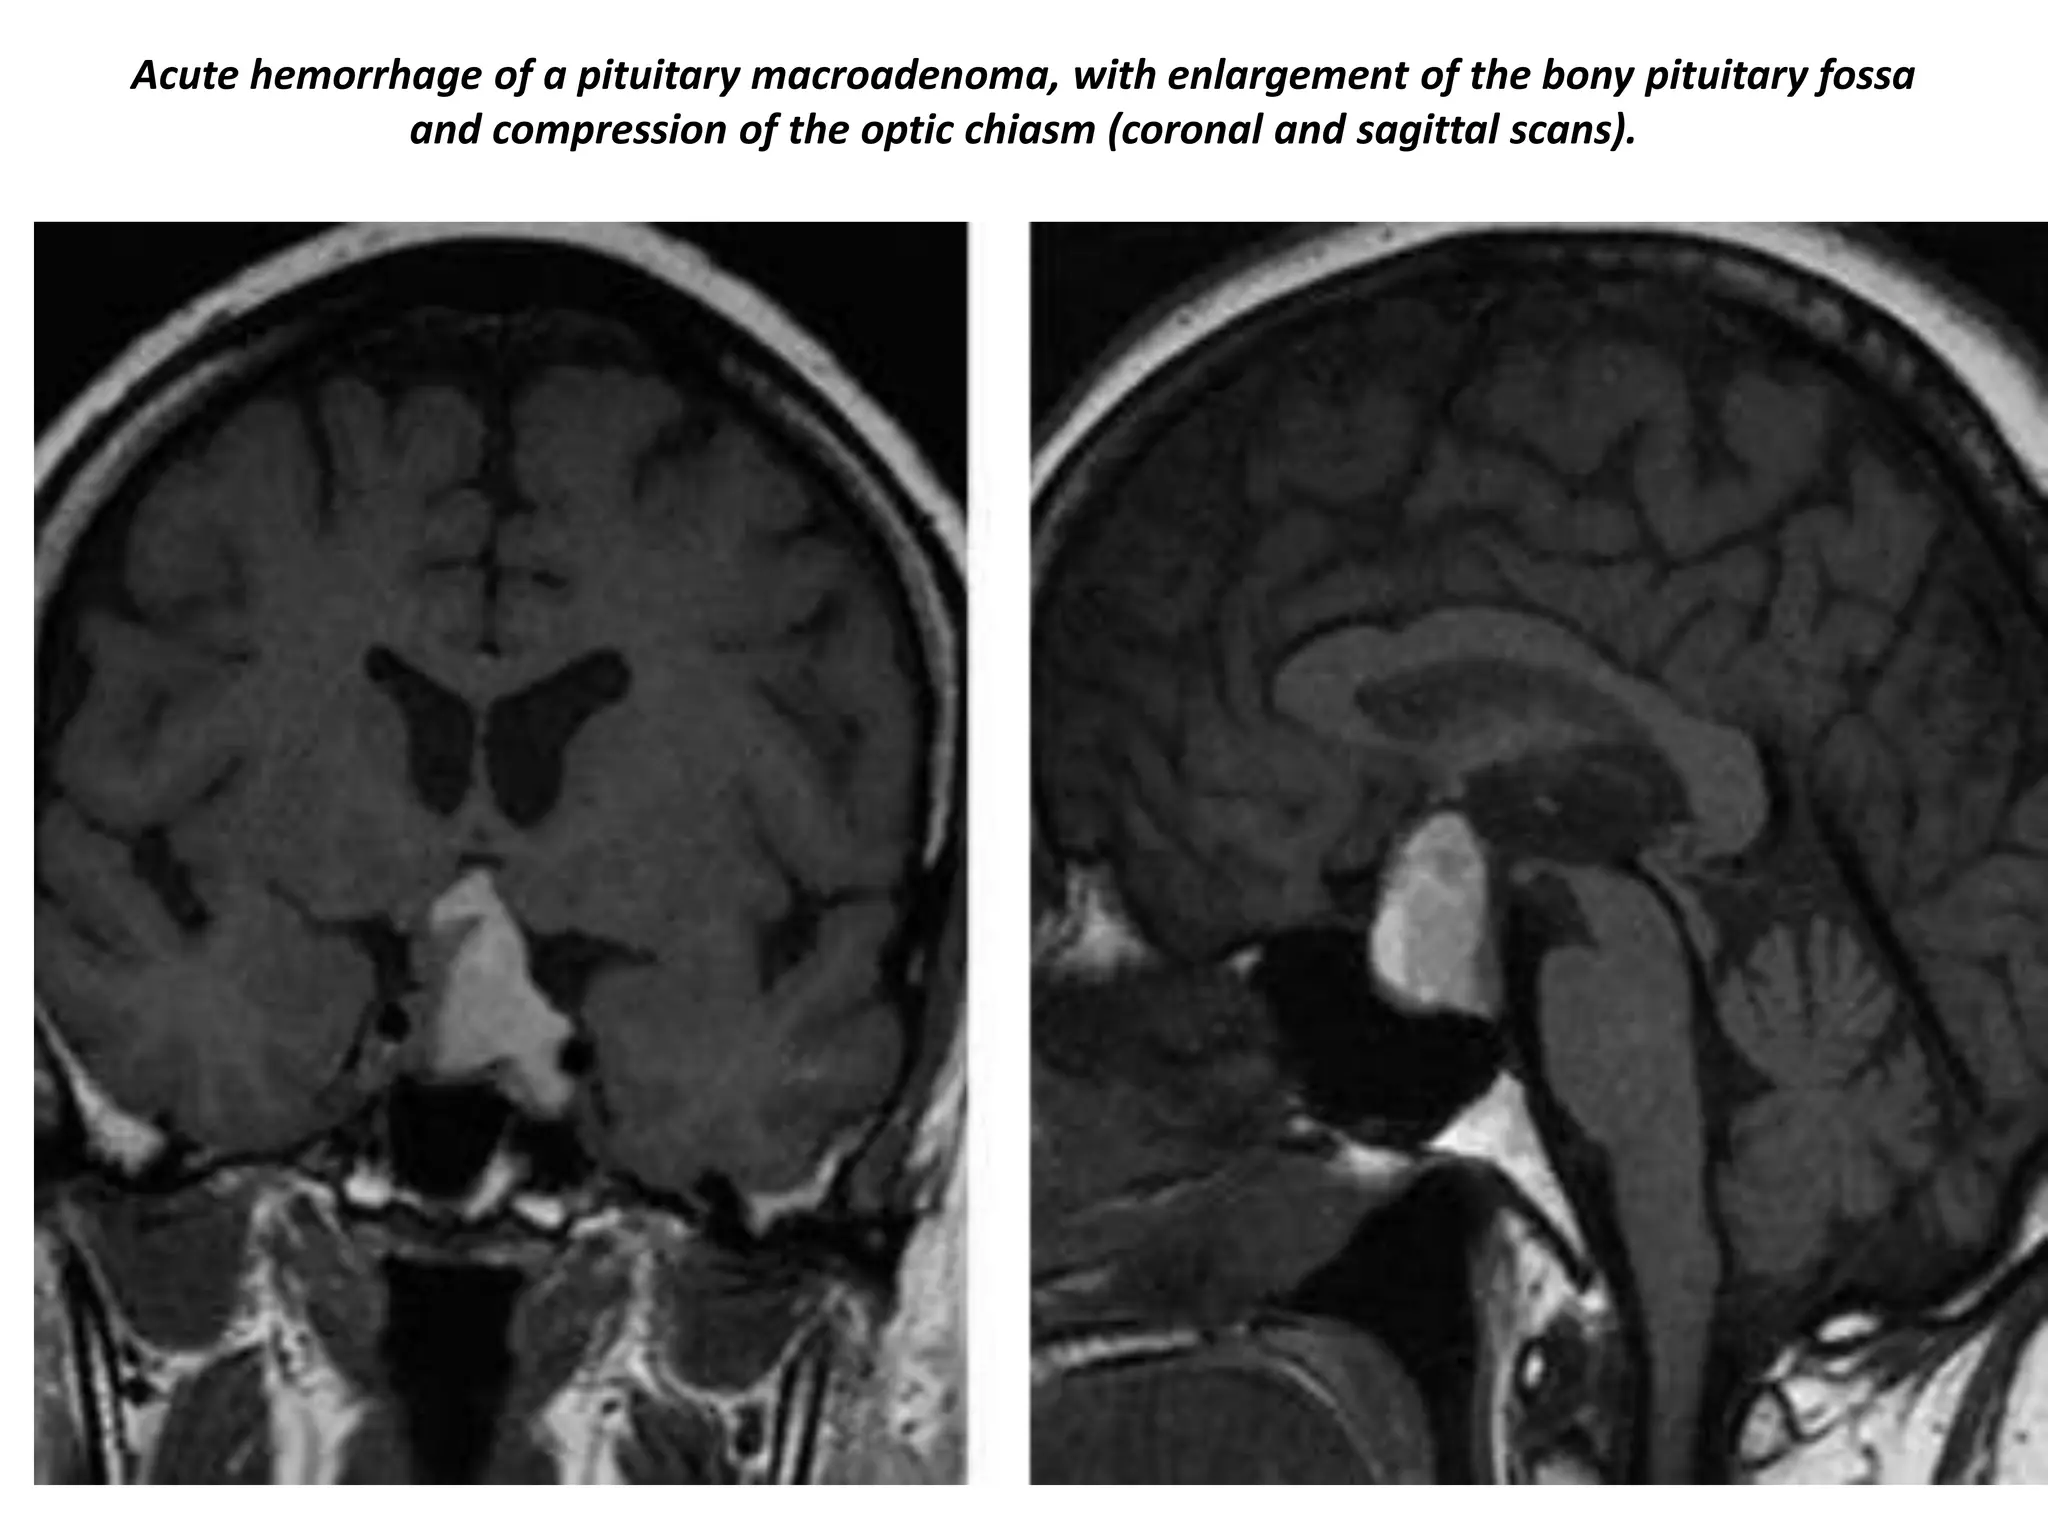

By definition, pituitary macroadenoma are adenomas over 10mm in size. They tend to be soft, solid lesions, often

with areas of necrosis or hemorrhage as they get bigger. As they grow, they first expand the sella turcica and then

grow upwards. In this example of a pituitary macroadenoma there is suprasellar extension with elevation and

compression of the optic chiasm. Because they are soft tumors, they usually indent at the diaphragma sellae, giving

them a 'snowman' configuration. This is one feature that can help distinguish between a pituitary macroadenoma

and a meningioma. Another feature which can help differentiate them is enlargement of the sella turcica - this

generally only occurs with pituitary macroadenoma that originate in the sella.

Aggressive pituitary adenomas are the most common lesions of the skull base with

destruction and extension to the sphenoid sinus.

Acute hemorrhage of a pituitary macroadenoma, with enlargement of the bony pituitary fossa

and compression of the optic chiasm (coronal and sagittal scans).